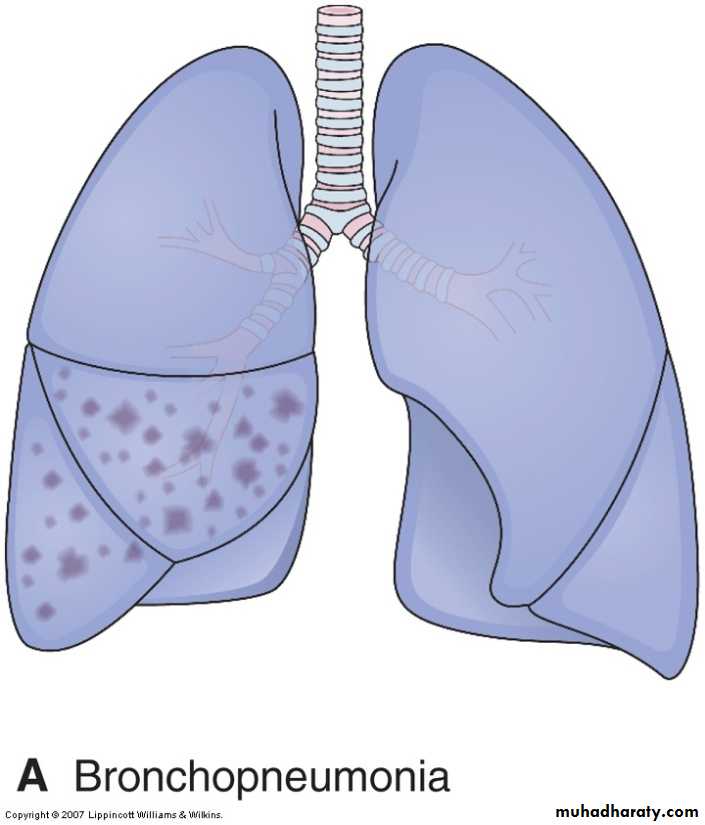

Acute bacterial pneumonias can present as one of two anatomic and radiographic patterns, referred to as bronchopneumonia and lobar pneumonia.1- Bronchopneumonia implies a patchy distribution of inflammation that generally involves more than one lobe . This pattern results from an initial infection of the bronchi and bronchioles with extension into the adjacent alveoli.

Bronchopneumonia. Gross section of lung showing patches of consolidation (arrows